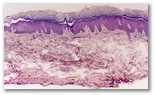

Diagnostico